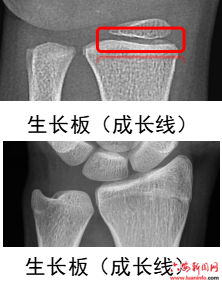

1、什么是骨龄?

人的生长发育有两个“年龄”:生活年龄(年纪)和生物年龄(骨龄)。骨龄就是指骨头的年龄,每个阶段骨骼的成熟度都不同。骨龄可真实地反应儿童的生物年龄,根据骨龄可客观地评价儿童生长发育水平,一般通过儿童的左手正位X光片来评估。想让孩子有一个理想的成年身高,应尽早定期检测骨龄,并进行身高体重管理。